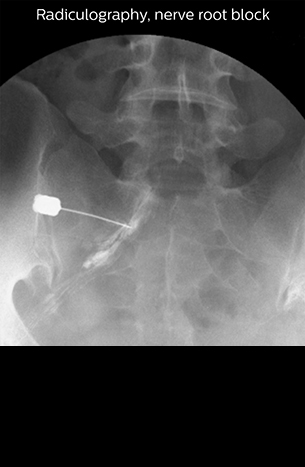

“In such case, we would then browse through axial T2-weighted MR images slice by slice and mentally reconstruct the actual situation based on both radiculography and MRI. Fortunately, NerveVIEW can now very well show nerve courses and presence of nerve compression or edema in one single image series.” “We have often seen NerveVIEW directly depict details of the nerve compression that were not observed by radiculography. Therefore, we think that with NerveVIEW we can reduce the number of invasive examinations, especially for some patients with lumbar plexus symptoms.”

“Before NerveVIEW, diagnosis by MRI alone was sometimes difficult, unless there was a strong suspicion based on clinical symptoms,” says Shoji Yabuki, MD, DMSc, Orthopedic surgeon at Fukushima Medical University School of Medicine. “This is why we routinely perform selective lumbosacral radiculography (nerve root block) and x-ray in such cases. However, radiculography can only depict nerves as far as the contrast agent reaches. When a nerve is distorted by compression, the contrast agent will not pass through this compressed area, preventing us from evaluating the full nerve compression.”

“NerveVIEW can clearly show nerve courses and presence of nerve compression. However, when multiple abnormalities are seen, it can still be hard to determine which nerve is causing the symptoms,” says Dr. Yabuki. “In our experience so far, we see abnormal findings on NerveVIEW in about 70% of elderly patients. As the pain is usually caused by only one nerve, we thus need to find the exact corresponding nerve.” “With a nerve root block, the patient's pain is improved by infiltration of local anesthesia directly around the nerve root considered to be responsible. Knowing such nerve root block findings prior to image interpretation, helps to easily recognize abnormal findings on NerveVIEW as well. In other words, without a priori knowledge, based on symptoms and/or nerve root block findings, we must be aware of the possibility of overdiagnosis.”